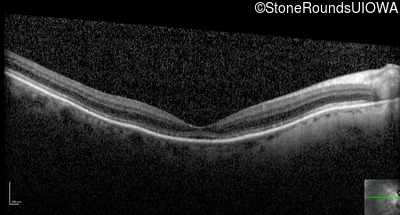

Optical Coherence Tomography - Right - 20/250

Exemplar / OCT Stack